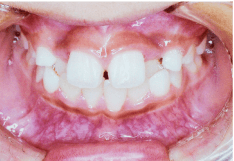

- 叢生(そうせい)

- 歯がでこぼこに並んでいる状態のことをいいます。この状態は歯磨きのときにブラシがしっかりと届きにくく歯垢が残りやすいため、虫歯や歯槽膿漏の原因になります。